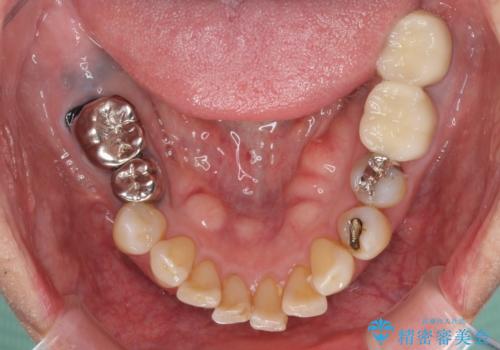

- 奥歯を他院で抜歯した後、インプラント治療を希望とのことで来院された患者様です。

ブリッジの支台を抜歯したことで2本のインプラントが必要であり、その後方はインプラント埋入に必要な骨量が不足していたため、上顎洞粘膜の挙上を行うこととしました。

また、残っている最後方歯は手前に倒れてきていたため、部分矯正により奥に移動させてから、インプラント埋入を行うこととしました。